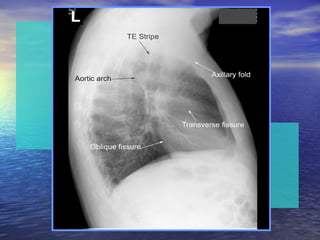

Surface projections of the lungs and the pleural cavities The apex of each lung projects above the medial third of the clavicle. Interlobar fissures The oblique fissure begins posteriorly in the upper thoracic region, crosses the 5th and 6th ribs, curves laterally to the midaxillary  line, and courses along the lower border of the 6 th  rib to the lateral border of the sternum. The right lung's horizontal fissure courses along the lower border of the 4th rib from the midaxillary line to the lateral border of the sternum

Surface projections ofthe lungs and the pleural cavities The apex of each lung projects above the medial third of the clavicle. Interlobar fissures The oblique fissure begins posteriorly in the upper thoracic region, crosses the 5th and 6th ribs, curves laterally to the midaxillary line, and courses along the lower border of the 6 th rib to the lateral border of the sternum. The right lung's horizontal fissure courses along the lower border of the 4th rib from the midaxillary line to the lateral border of the sternum